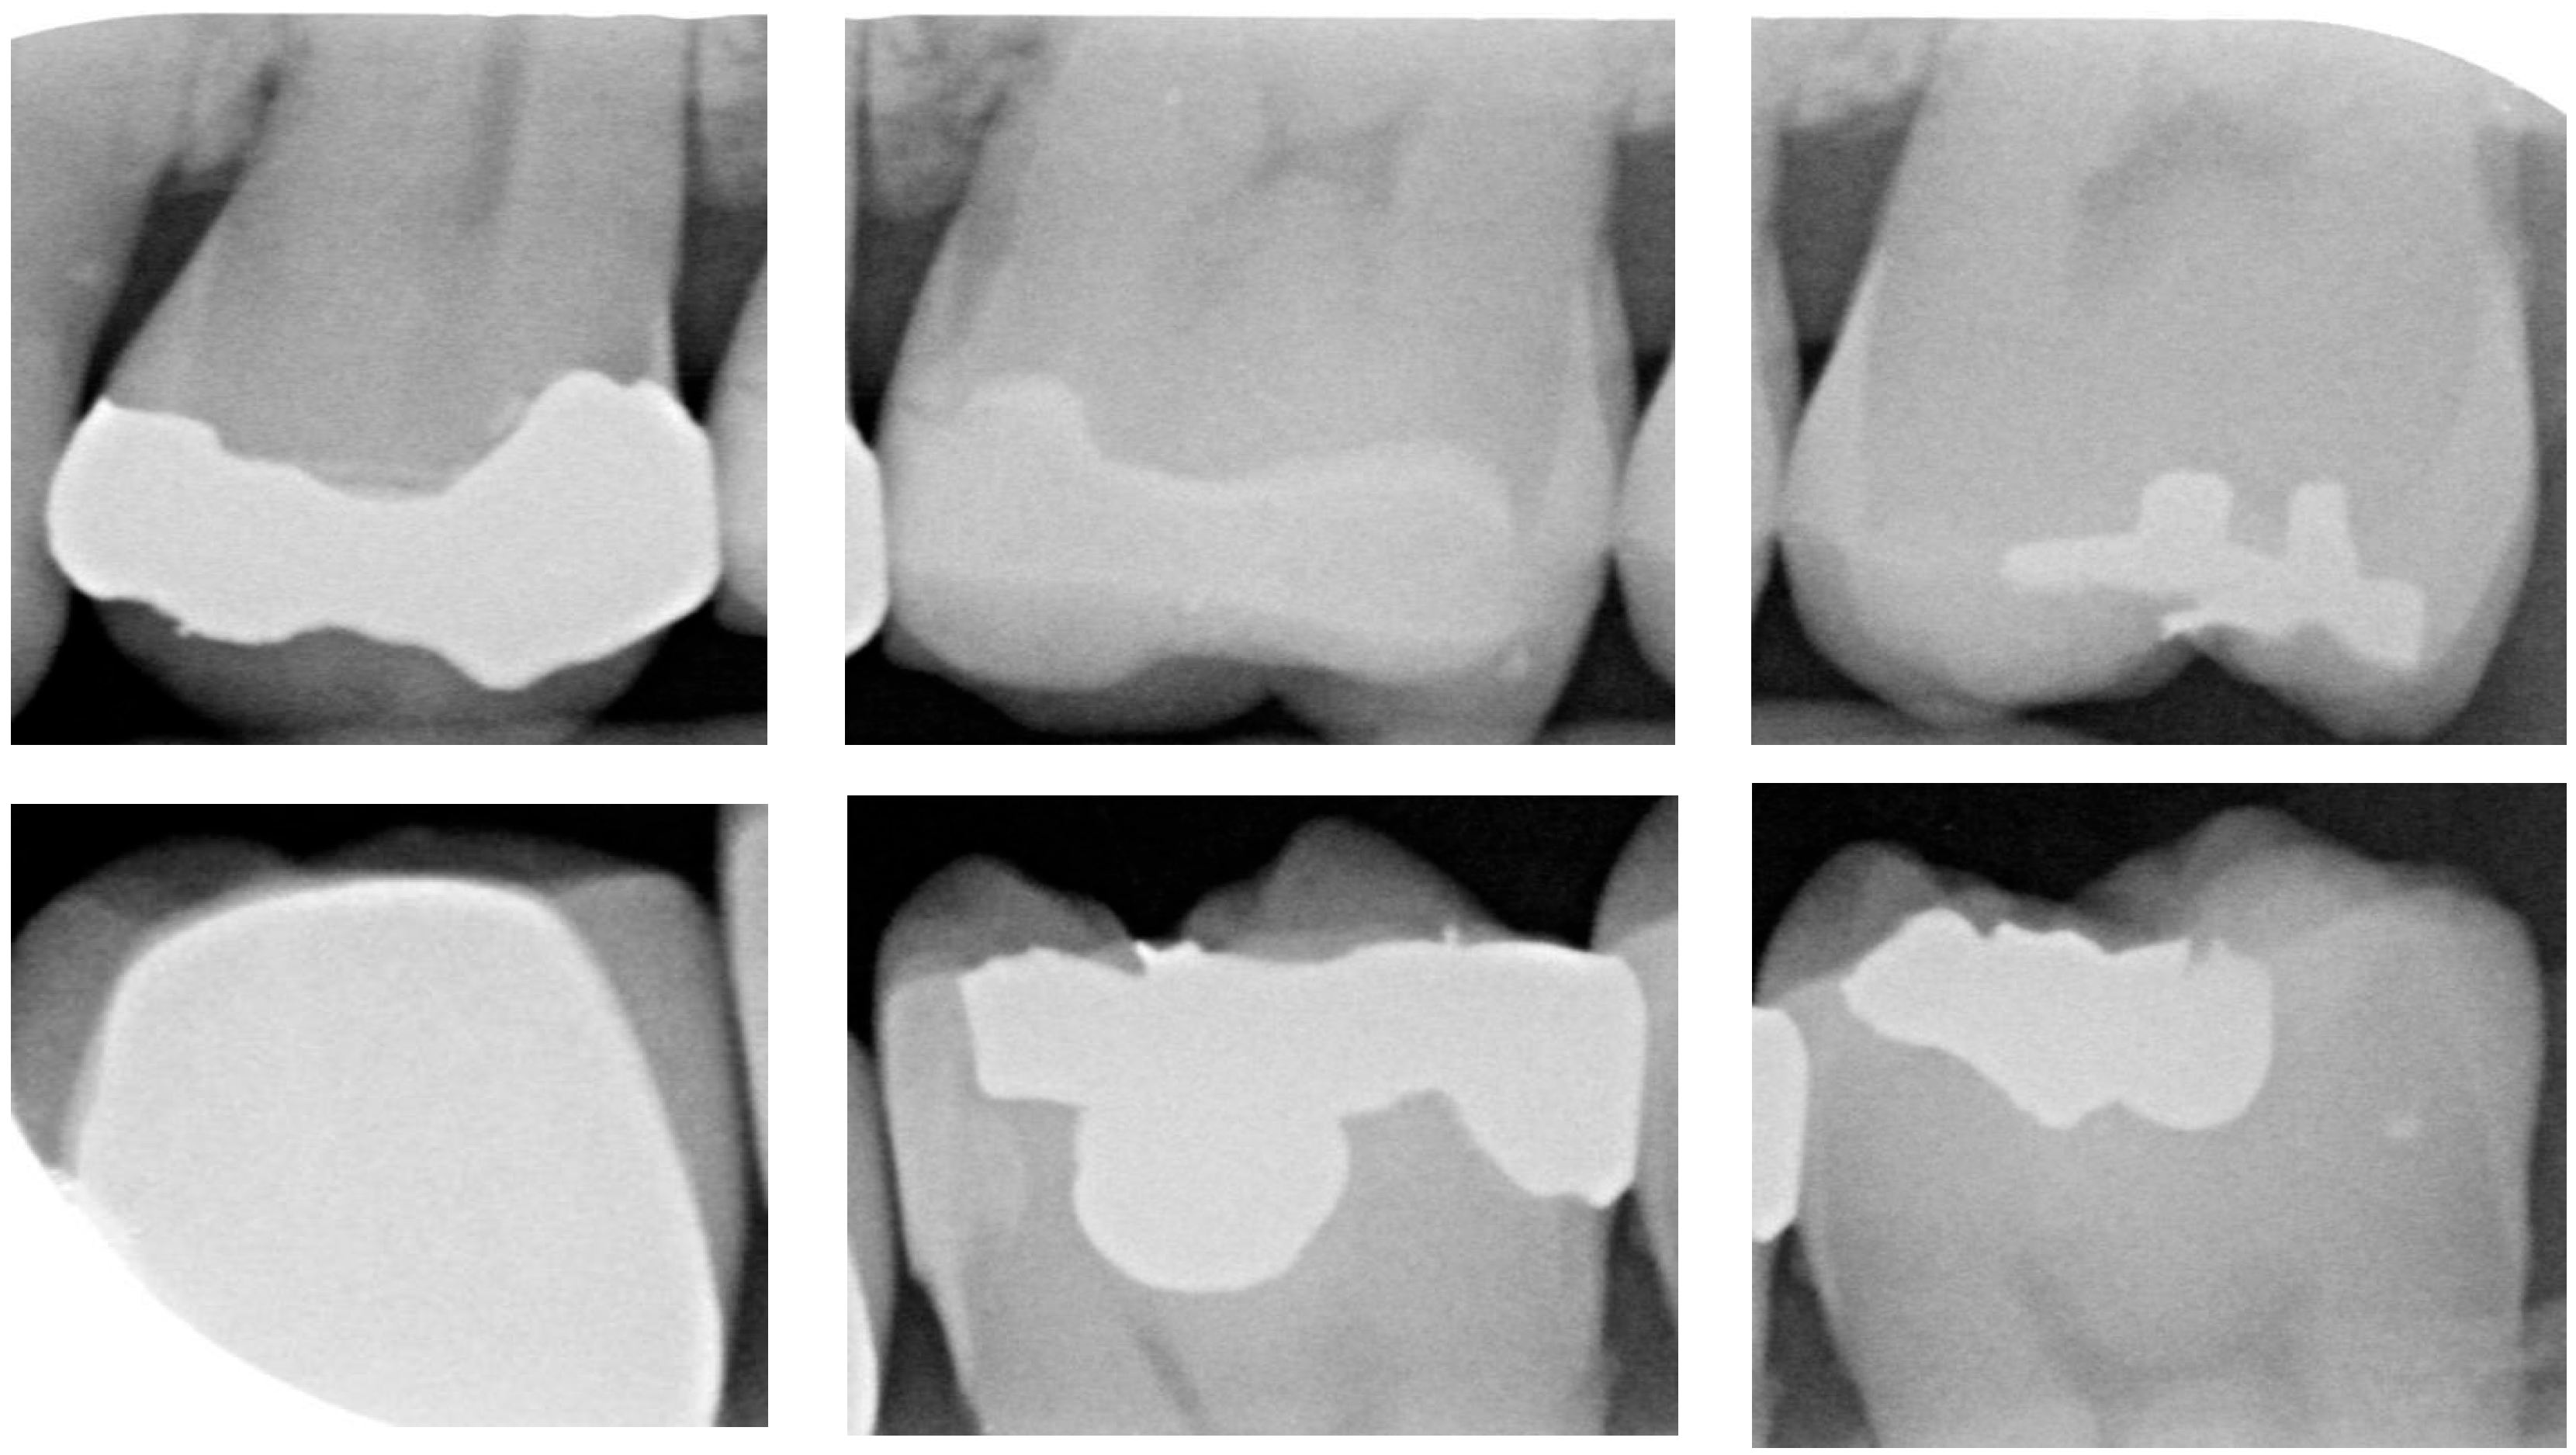

For CNN models, having an adequate amount of data is crucial to ensure effective learning and generalization performance. When the training sample size is limited, models are prone to overfitting or may fail to achieve good generalization performance. After applying the image-segmentation technique developed in this study, a total of 1340 images of individual teeth were obtained, including 428 images with dental calculus and 912 images without dental calculus. To balance the data quantity and to reduce overfitting issues, this study employed random image-flipping and mirroring techniques for data augmentation. This study set the dataset to include 670 images with dental calculus and 670 images without dental calculus. Dental calculus images were randomly selected for flipping or mirroring, while non-dental calculus images were also randomly selected to form the dataset for CNN training and validation. The detailed breakdown is presented in Table 4. A total of 80% of the image dataset was randomly chosen as the CNN training dataset. The remaining 20% of the dataset was used as the validation-image dataset. Moreover, the CNN training dataset was split into a 7:3 ratio for the training and testing datasets, and the training image as shown in Figure 9.

Figure 9.

Data augmentation results. (a) Dental calculus. (b) Without dental calculus.